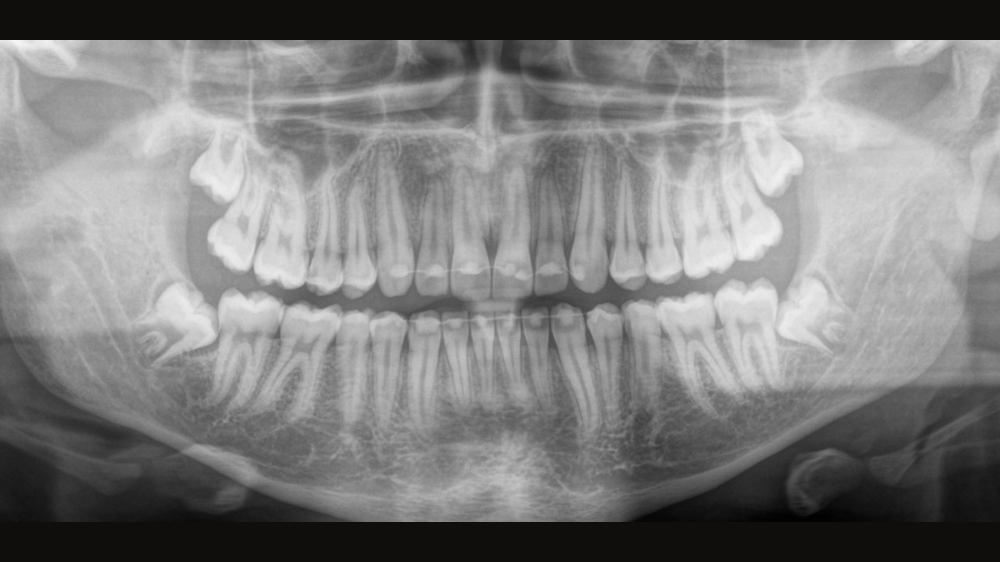

幅広い治療を提供する診療所向け大FOV、および高画質の2D/3Dシステムです。歯科医師などの関係者と協力して開発されたAxeosは、デンツプライシロナのあらゆるレントゲン装置の中で最も多くの機能を提供することができます。この歯科用レントゲン装置は、優れた画質とユーザーが用途に応じて選択できる3D撮影範囲の機能に加え、患者さんの快適性を高めるための工夫がなされています。Axeosは、パフォーマンスと快適さの品質を提供するだけでなく、一体型のバイトブロックを格納できるキャビネット、そして患者さんの緊張を和らげるためのアンビエントライトなど、デザイン面での受賞歴があります。

優れたパノラマ画像を取得するには、適切なフォーカスが重要です。オートフォーカス機能を使用すると、可能な限り高い鮮明さでフォーカスした画像を、自動的に得ることができます。弊社の画像診断装置は、1サイクルで数千の個別画像を撮影し、顎が最適な位置にある領域を自動的に特定することができる機能を有します。手動で追加の手順を行わなくても、鮮明な画像が最終的な画像として表示されます。